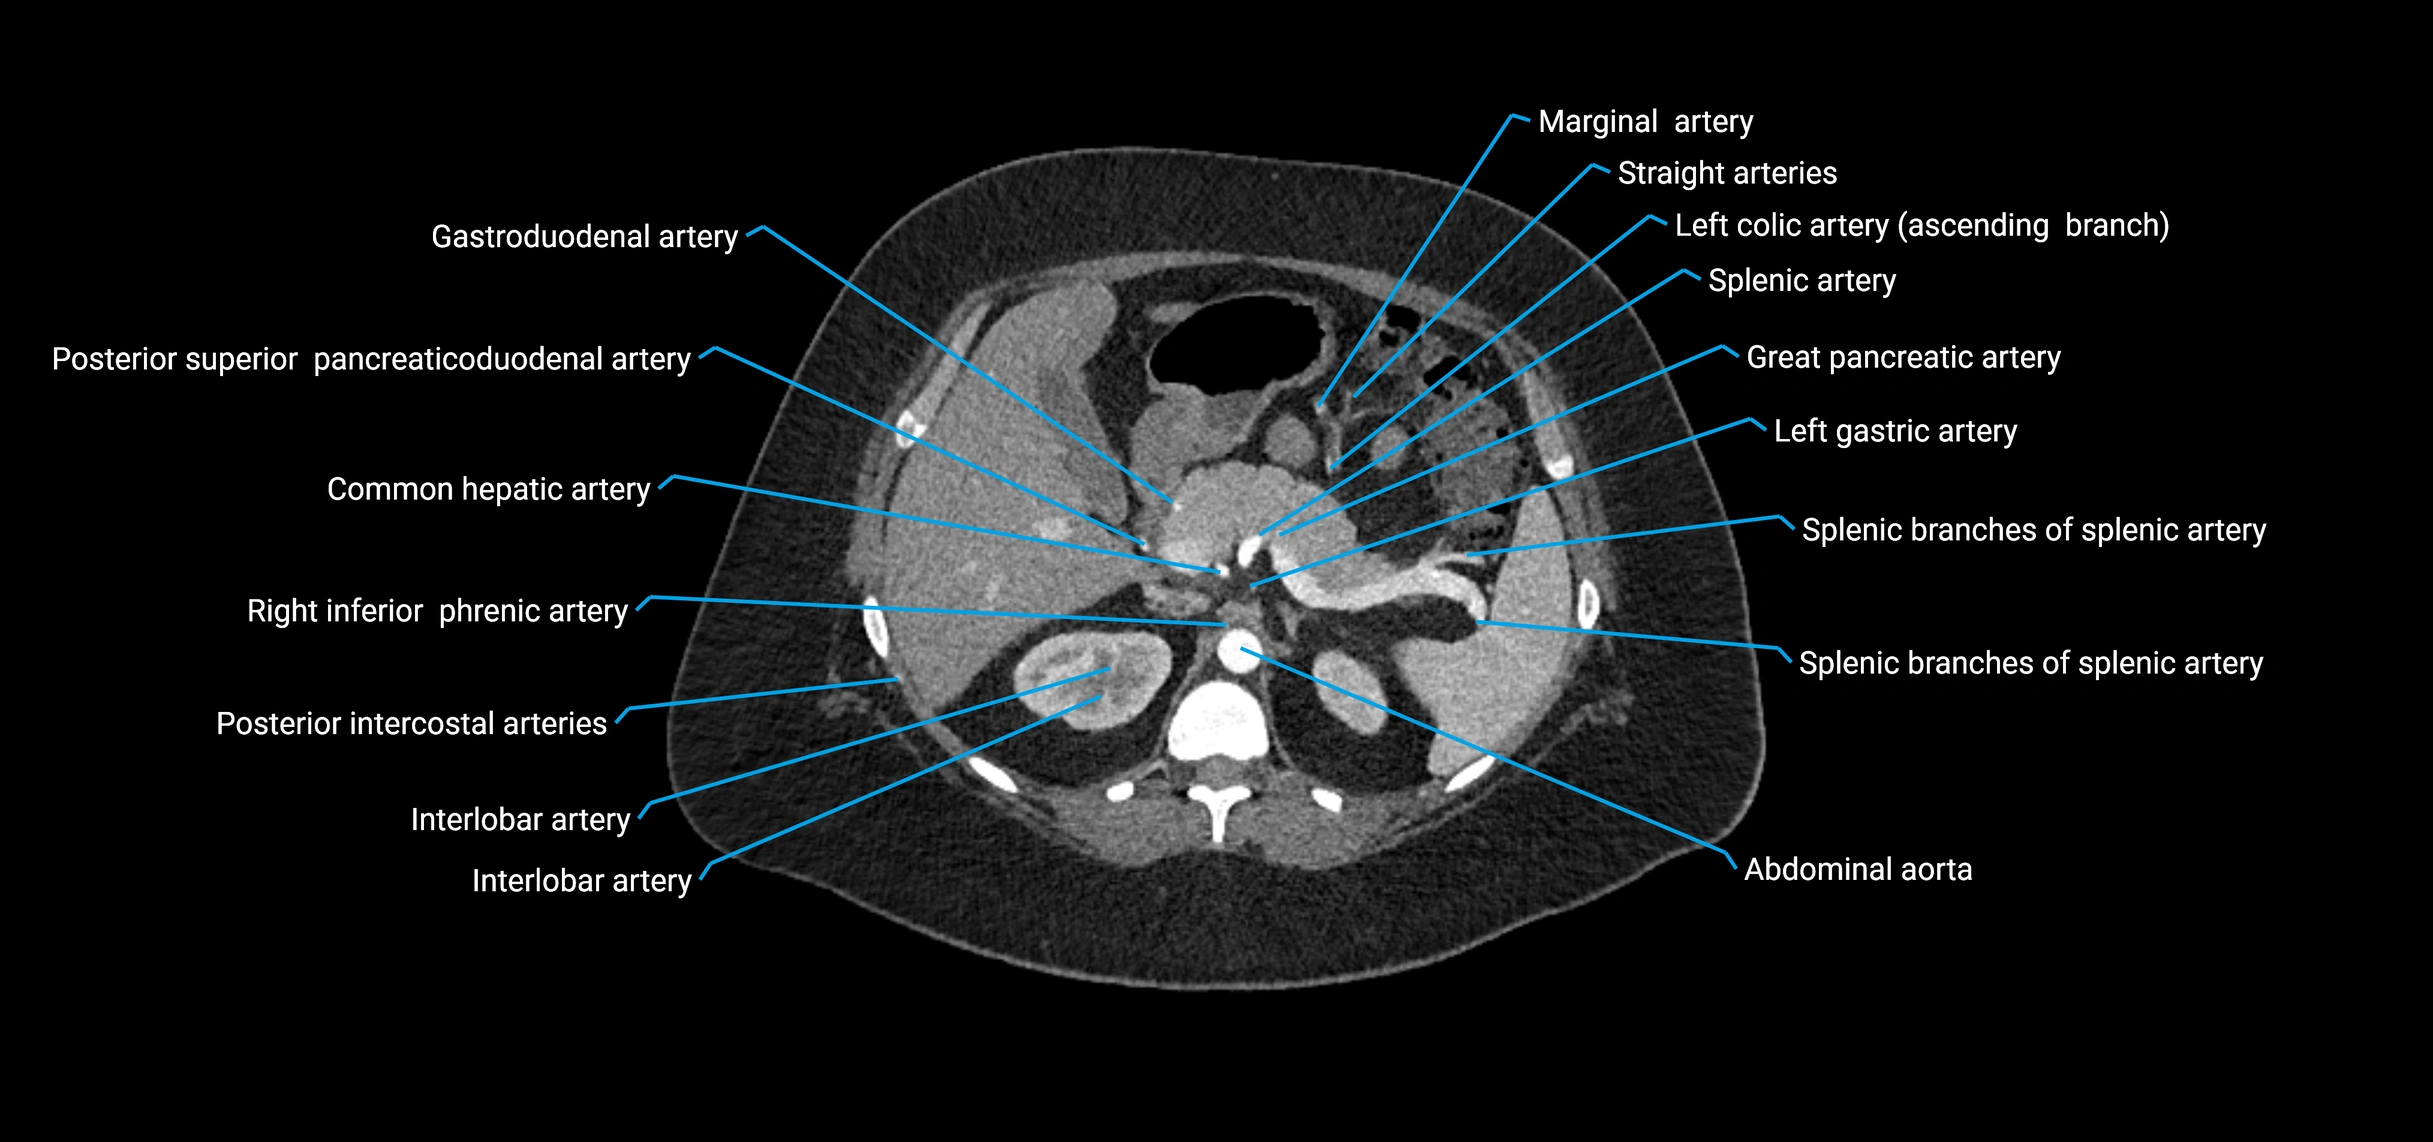

Contrast-enhanced CT (CTA):

• Gold standard for abdominal aortic imaging

• Provides excellent detail of lumen, wall, aneurysm, thrombus, and branch vessels

• Multiplanar and 3D reconstructions help in aneurysm measurement, stent graft planning, and dissection evaluation

• Detects acute rupture, traumatic injury, or occlusion with high sensitivity